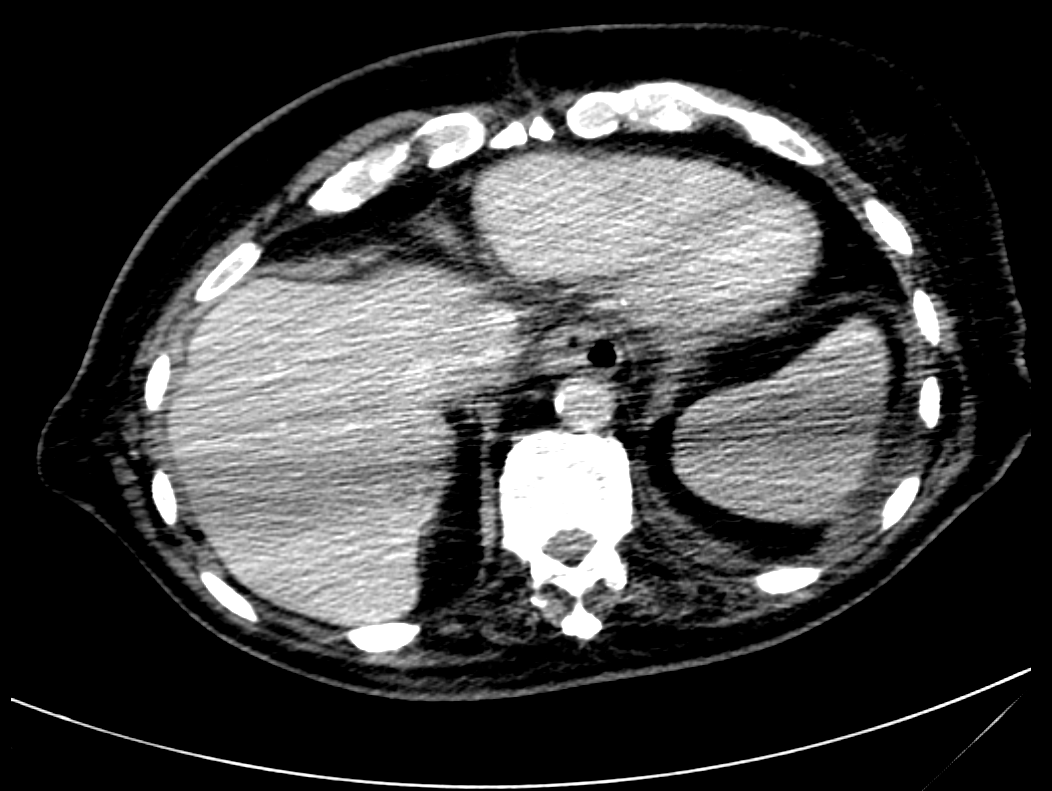

Visual results of our algorithm compared to the reference contour for 6 cases in axial and sagittal view are depicted in Fig. 5. From the sagittal views it can be observed that manual contours are not as smooth as the automatic contours, which could be due to the breathing artifacts. The use of convolutions and post-processing in 3D aids at processing information of the 3D context through several slices, which is reflected in the smoother automatic contours shown in these images. On the other hand, from the axial views we can realize that, despite of the similarity with respect to neighboring tissues, and heterogeneity of the inner region of the esophagus, our automatic system provides contours that are comparable with the reference standard.

Refer to caption a) clinical case 09 sagittal view Refer to caption b) clinical case 13 sagittal view Refer to caption c) clinical case 20 sagittal view

Refer to caption d) clinical case 09 axial view Refer to caption e) clinical case 13 axial view Refer to caption f) clinical case 20 axial view

Refer to caption g) public case 01 sagittal view Refer to caption h) public case 12 sagittal view Refer to caption i) public case 24 sagittal view

Refer to caption j) public case 01 axial view Refer to caption k) public case 12 axial view Refer to caption l) public case 24 axial view

Figure 5: Contouring results for 6 cases in different views. The green line indicates the reference standard, the red line depicts the contour generated by the proposed algorithm.